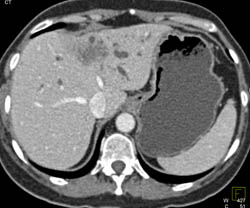

Liver Abscess